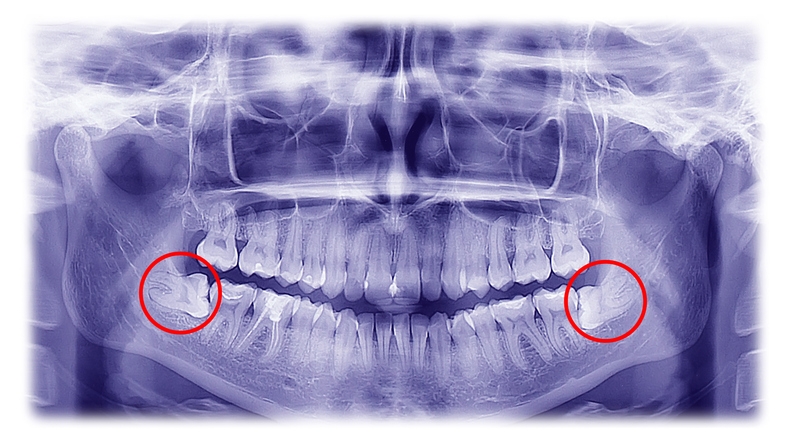

Before you can undergo any form of impacted wisdom teeth removal, you will first meet your oral surgeon for a consultation. During the visit, you will be required to provide your dental and medical history to your surgeon. This is to make sure that you do not have any prior problems that may interfere with the recommended treatment. Your dentist will then conduct a thorough examination of the state of your mouth, jaw, and teeth. He/she will also take x-rays of your wisdom teeth as well as the neighbouring teeth before any treatment can commence.

When a wisdom tooth is impacted, the chances are high that your dentist will recommend extraction as the ideal solution. If ignored, it is almost certain that it will cause some complications especially if it is located on the lower jaw. For proper wisdom teeth removal, the dentist needs to carry out a proper diagnosis. During the diagnosis, the dentist will assess any signs of infections that include swollen or red gums. He/she will also take an x-ray to determine the position of the impacted wisdom tooth and the extent of damage caused by the tooth. Once all that is done, your dental surgeon will then proceed to a wisdom tooth removal procedure.